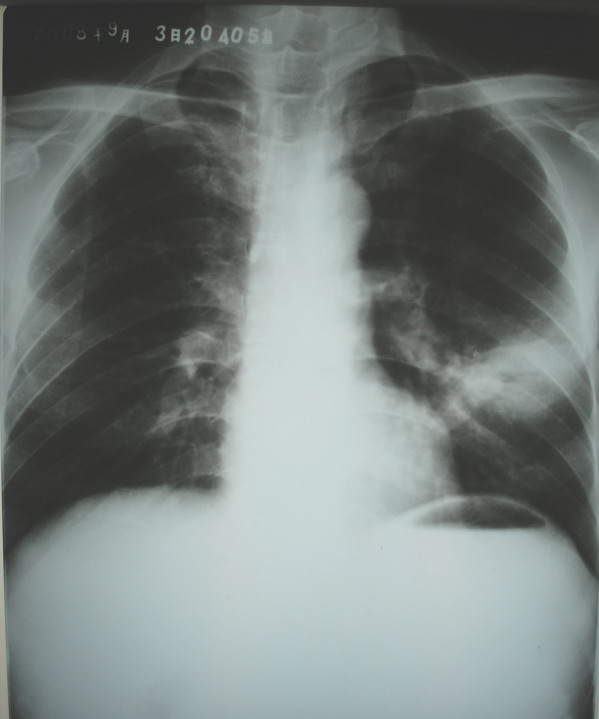

男,42岁,发烧、咳嗽、身体消瘦月余.

左肺上叶占位,结核可能性大,建议做结核菌素试验

左肺门影浓深,不排除左上肺段型肺ca伴舌段不张,炎变可能.建议ct

左肺上叶感染性病变(肺脓肿?肺结核?);建议抗炎治疗后复查。

左肺上叶感染性病变,肺脓疡可能性大。建议抗炎治疗后复查,除外肺结核。

侧位可见后壁偏心空洞,有液气平面,tb?肺ca?